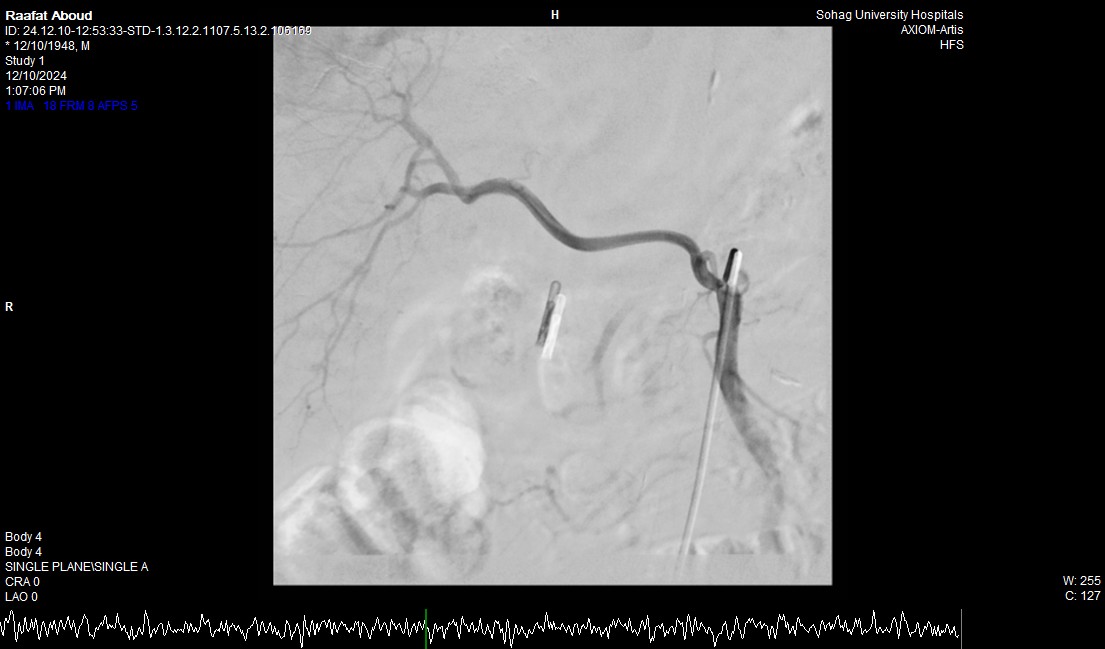

وأضاف الدكتور أحمد كمال المدير التنفيذي للمستشفيات الجامعية جامعة سوهاج، أنه بعد إجراء الفحوصات للمريض تبين وجود قرحة كبيرة بالإثنى عشر وشريان نازف، حيث نجح الفريق في التحكم المبدئي بالنزيف عن طريق تركيب مشبك معدني بالمنظار وحقن للقرحة النازفة، ثم تم استدعاء فريق أطباء وحدة الأشعة التداخلية على الفور وتم عمل غلق للشريان النازف بشكل عاجل من خلال جهاز القسطرة.

وأوضح الدكتور محمد زاكي رئيس قسم الأشعة، أن مثل هذه الحالات تعد من الطوارئ الطبية الخطيرة والتي تستوجب عمل قسطرة شريانية عاجلة لغلق الشرايين النازفه، مشيرًا أن وحدة الأشعة التداخلية تم تزويدها بجهاز أشعة محوري متقدم لاجراء مثل هذه الحالات، وأن هذا النجاح هو نتيجة لتعاون أقسام المستشفى مع وحدة الأشعة التداخلية لتقديم خدمة مميزة للمرضى.